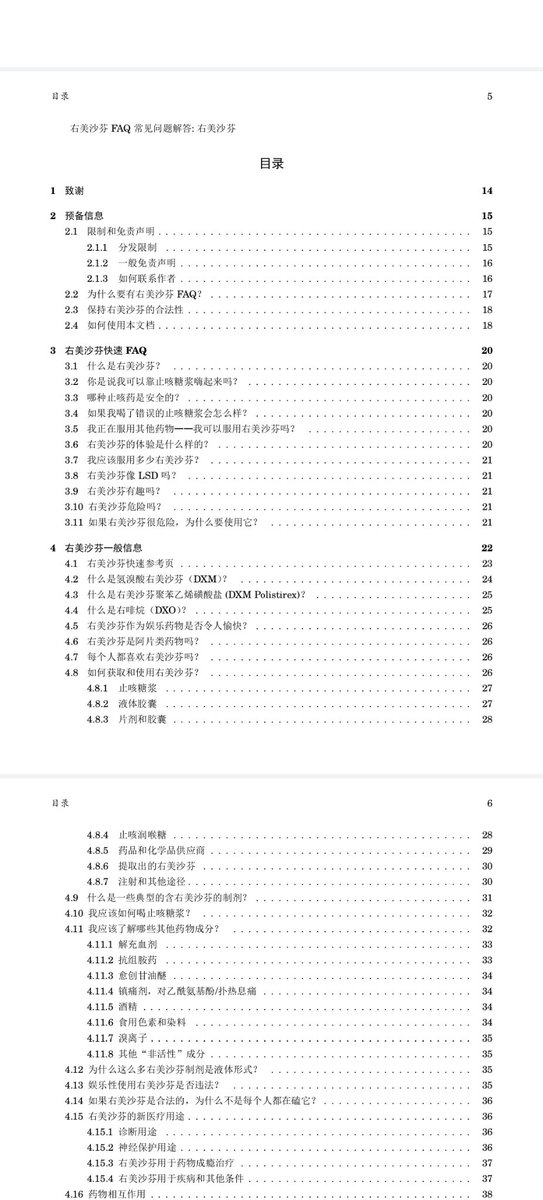

关于后藤提到过的“反解离”

首先,从定义上讲,“反解离(anti-dissociative)”并不是一个标准的医学术语或者广泛认同的药理学分类。在正规资料,比如医学文献、维基百科、精神药理学教科书中,目前并没有“反解离药物”这个正式概念。

看上去像是为了描述某类特定效应而创造的术语(可能是nmda受体活性增强),用来对抗因NMDA受体拮抗剂(比如氯胺酮、DXM、PCP等)引发的解离体验(dissociation)。

那么更常见的是将其归入认知增强剂(cognitive enhancers),特别是改善认知连接性(connectivity)和现实感知(reality testing)的类型。

但其实在药理学上,单纯用“受体激动剂”来逆转“受体拮抗剂”的效应,有时会导致过度激活。

对于NMDA受体而言,过强的NMDA活化本身就与兴奋性毒性(excitotoxicity)和精神病样症状(psychotomimetic effects)有关,比如谷氨酸风暴可以引发严重的焦虑、妄想、乃至癫痫。

也就是说,简单地“激动-解除拮抗”在中枢神经系统是很危险的做法,尤其是对于易感个体(如有精神分裂素质的人)。

科学的处理方式一般是通过更细致的调节,比如微调NMDA/AMPA平衡、调节其他辅助途径(如GABA、5-HT、mGluR受体),而不是简单粗暴地用“NMDA增强剂”去顶回去。

而临床处理药物中毒中,其实医生更常用的做法是保守、支持性的治疗,比如补液,促进代谢,必要时镇静,以及监测生命体征防治并发症。

药物拮抗与受体激动之间,往往牵扯到的是复杂的适应性变化(receptor upregulation/downregulation),

不是简单的“给多一点刺激就能抵消”的关系